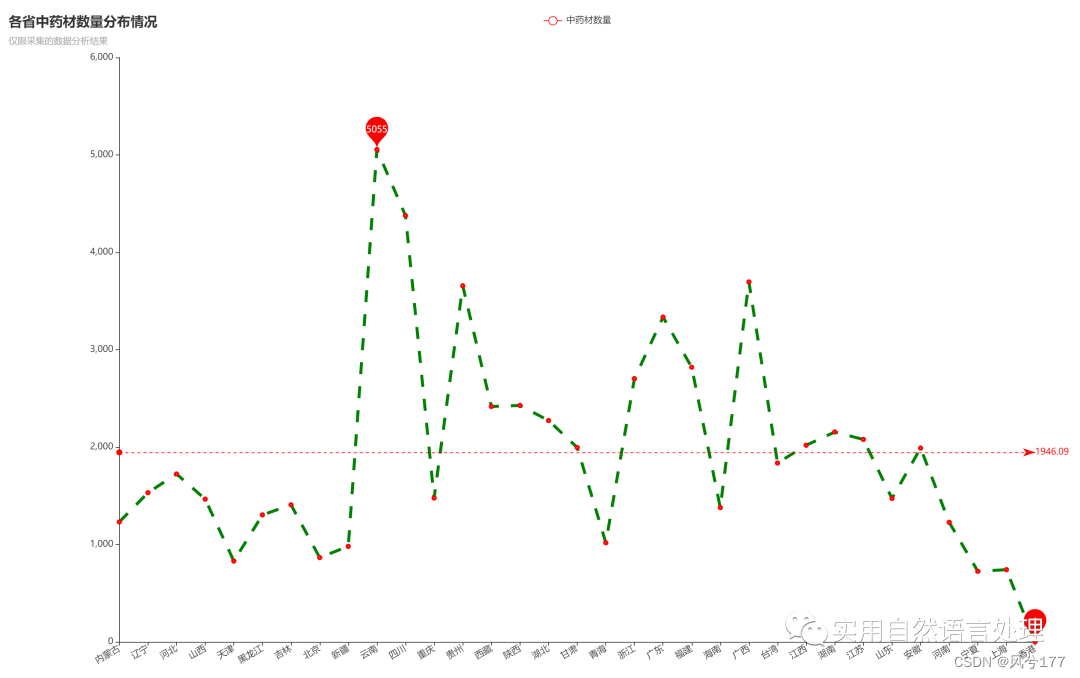

2.3 中药材知识图谱分析结果可视化

(1)中药材分布情况可视化